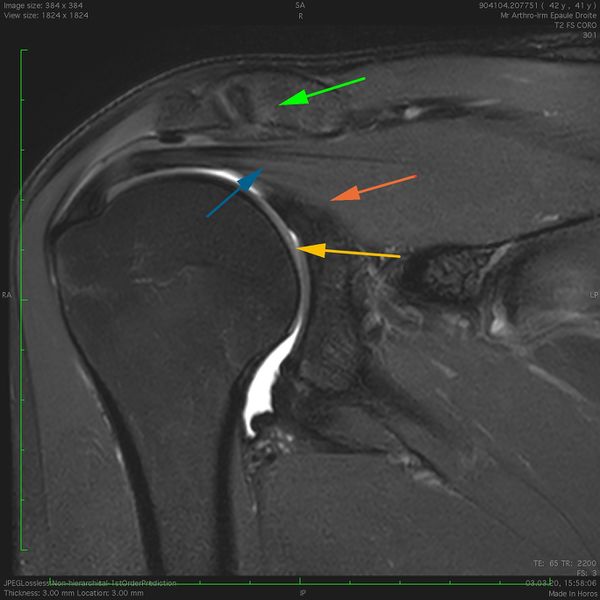

Sagittal magnetic resonance imaging (MRI) T2 fat saturation view of a right subcoracoid space, the coracoid process (green arrow) defines the superior border, the conjoint tendon (yellow arrow) form the anterior border, the glenoid (blue arrow) and the middle glenohumeral ligament (red arrow) serve as the posterior border.